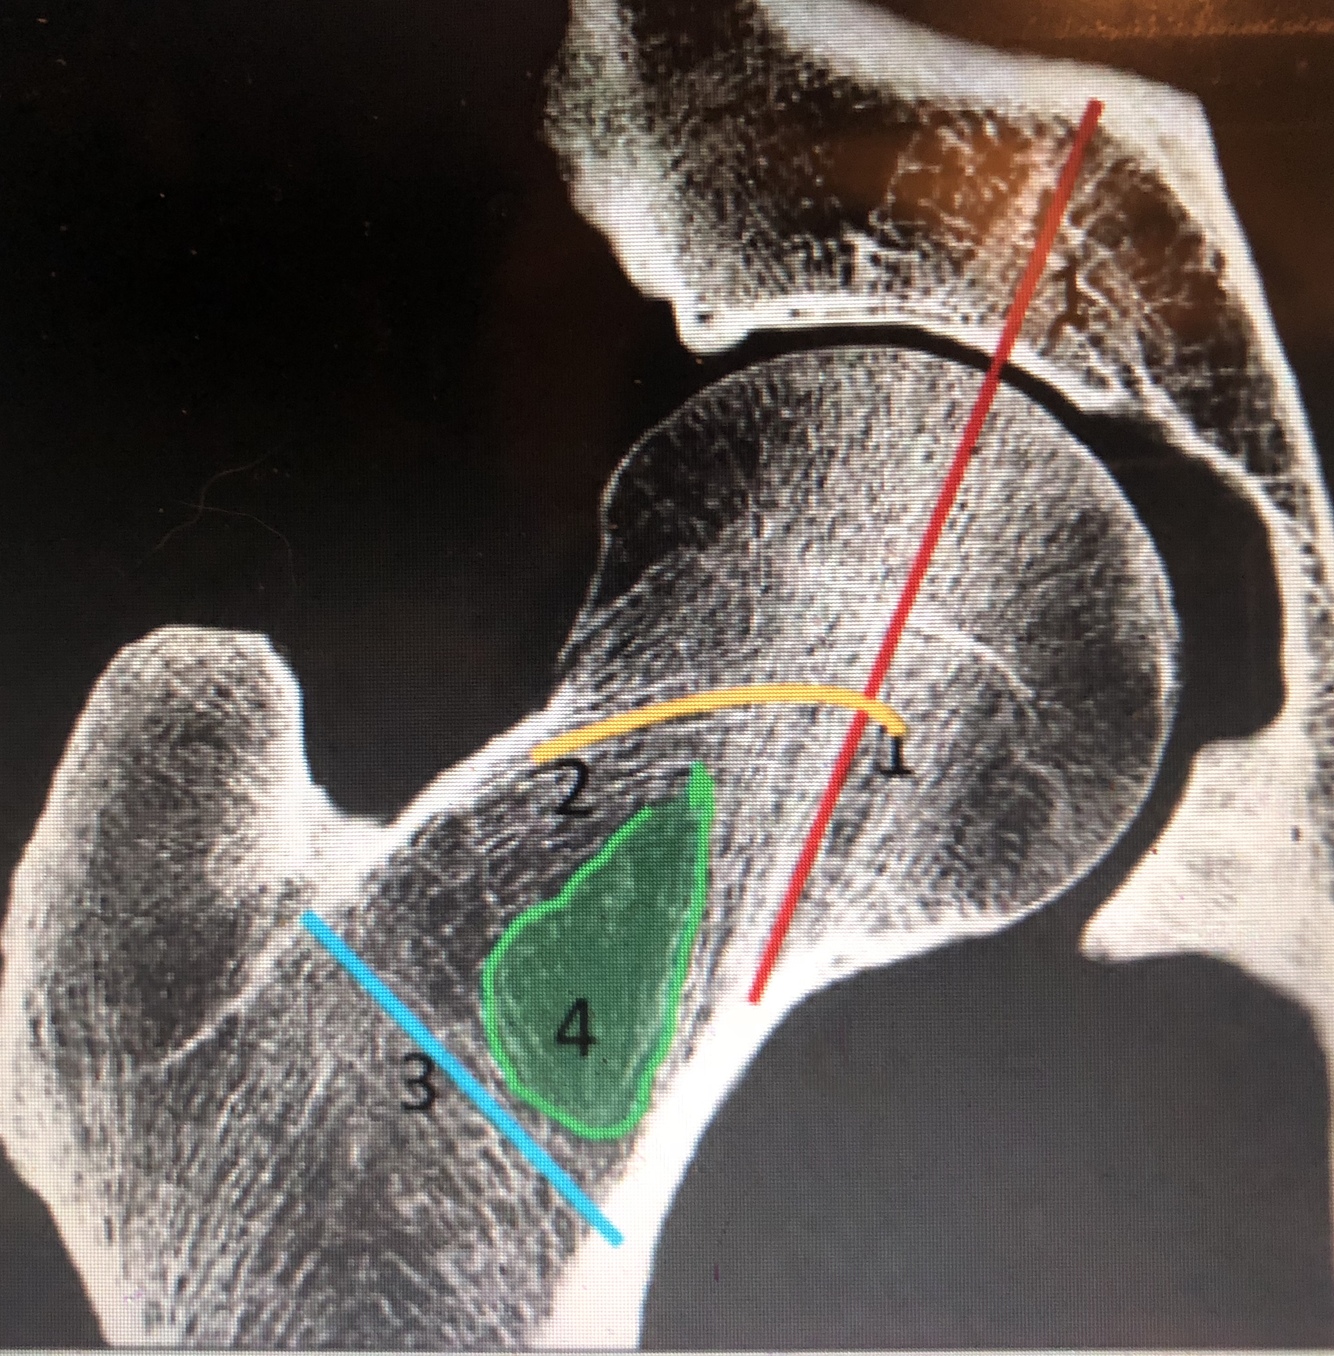

What is #1

lateral margin of femoral head

What is #2

medial margin of femoral head

What is the blue line/#3?

secondary compressive trabeculae

What is the yellow line/#2?

primary tensile trabeculae

What is the blue area/#4

Ward’s triangle is the relatively trabeculae-free area